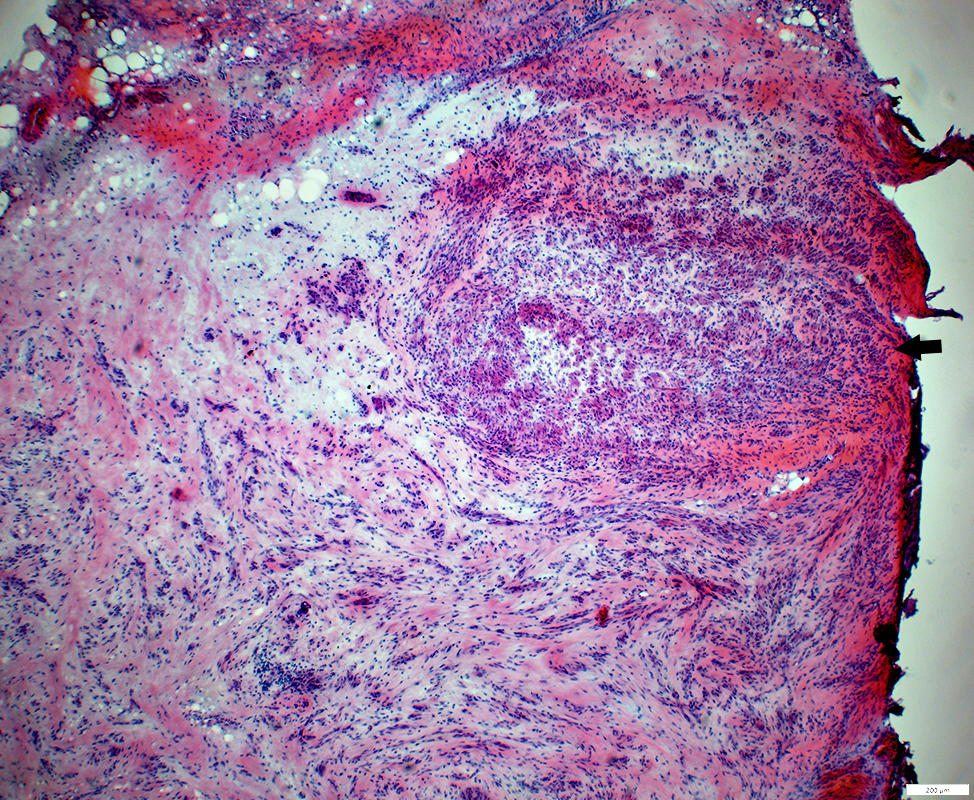

Regeneration: Aberrant Fascicles

H&E stain

Minifascicles

Varied sizes & orientations

Post-regeneration: Small fascicles with varied size and orientations

Neuroma: Multiple small fascicles containing myelinated axons

Neuroma

Varied sizes & orientations of axon clusters (fascicles)

Varied numbers of myelinated & non-myelinated axons in fascicles

Varied numbers of axons in fascicles

Several small fascicles separated by connective tissue

Each fascicle is surrounded by perineurium, 1 or several layers